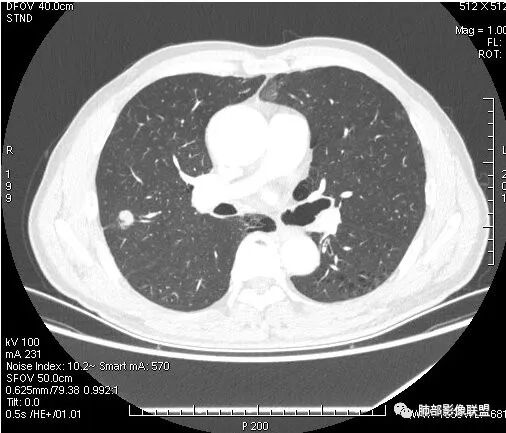

右上叶结节,轻分叶,结节有长短不一毛刺,结节周围GGO边界清,有血管集束征,肺窗结节周围似可见卫星灶,可见鬼脸征,良恶性征象都有,但GGO边界清,浸润性腺癌耍考虑,临床症状轻微,体捡发现,似可见卫星灶和鬼脸征,炎性肉芽肿TB或隐球菌要鉴别。

有卫星灶

虽然良恶性征象都有,但是这个病灶增强后坏死比较明显,如果是恶性:腺癌这样大小的结节坏死很少见,只有低分化腺癌可以坏死,但是低分化腺癌这种大小一般会有周围转移表现(叶间胸膜结节,癌淋或者淋巴结明显肿大),如果是鳞癌,收缩力,坏死情况以及没有支气管截断都不太支持,而且结节远端有几个小结节样改变,大家可能认为是血管,但我觉得应该是卫星灶。所以觉得隐球可能较大。壁胸膜的牵拉线也没有引起胸膜凹陷,比较纤细,至于病理中的丝状物不一定是真菌菌丝。

这个病例确实有很多隐球菌的特点,包括周围的卫星灶、周围的毛刺,它没有粗短的毛刺,它是稍长一点、柔弱一点的。我是觉得这个符合脐凹征,所以我觉得恶性不能排除,结果错了,是炎性。